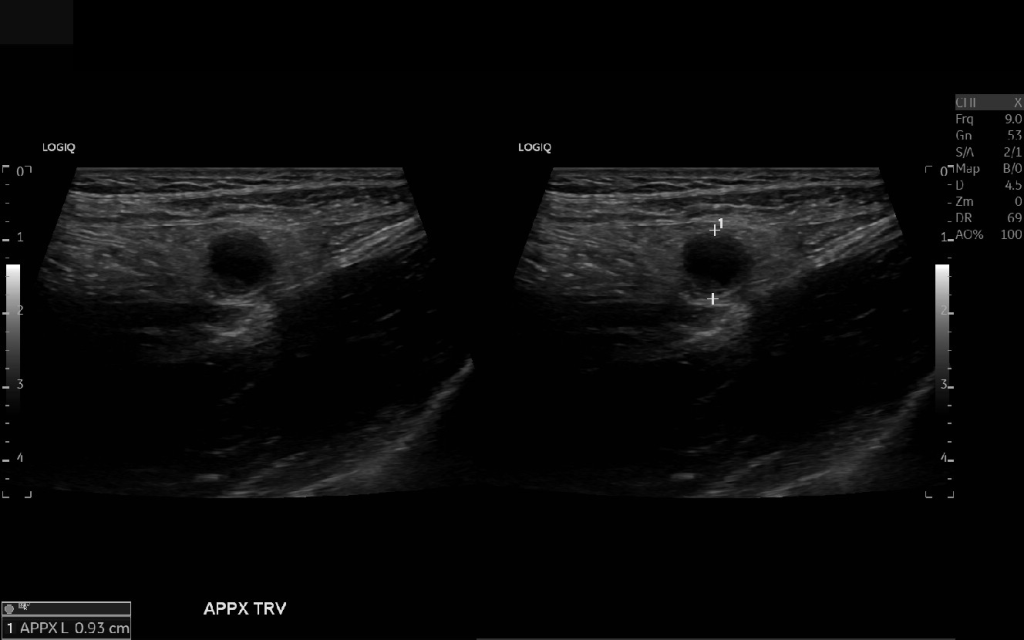

Appendicitis 12

0.9 cm positive appendicitis, with peripheral free fluid, and fat stranding.